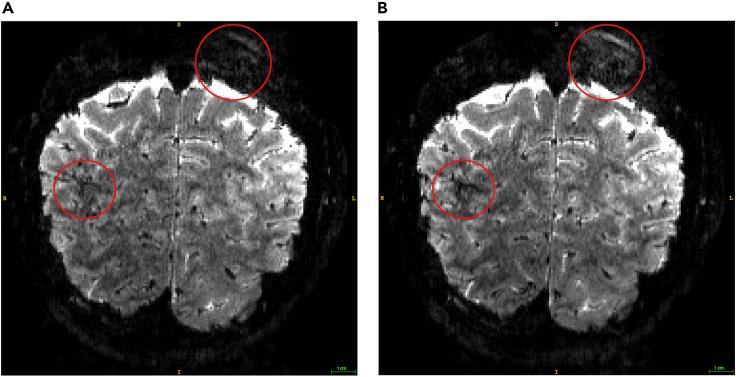

Ultra-high field (UHF) neuroimaging affords the sub-millimeter resolution that allows researchers to interrogate brain computations at a finer scale than that afforded by standard fMRI techniques. Here, we present a step-by-step protocol for using UHF imaging (Siemens Terra 7T scanner) to measure activity in the human brain. We outline how to preprocess the data using a pipeline that combines tools from SPM, FreeSurfer, ITK-SNAP, and BrainVoyager and correct for vasculature-related confounders to improve the spatial accuracy of the fMRI signal. For complete details on the use and execution of this protocol, please refer to Jia et al. (2020) and Zamboni et al. (2020).